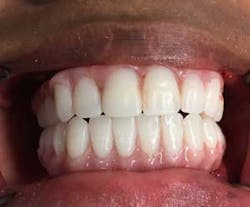

Provisional prostheses were then positioned and upon proper stability, function, and cosmetic appearance were torqued to 15 Ncm. At this point, the occlusion was evaluated; posterior occlusion was adjusted to be extremely light, and occlusion associated in the anterior region carried more inter-arch load (figure 11). (2)

The authors strongly believe that with the aggressive nature of her periodontal infection and associated types of bacteria, pathogenic to this aggressive disorder, complete tooth removal and rehabilitation with this protocol will provide this young patient with confidence and enthusiasm about living her life without dental complications (figure 12).